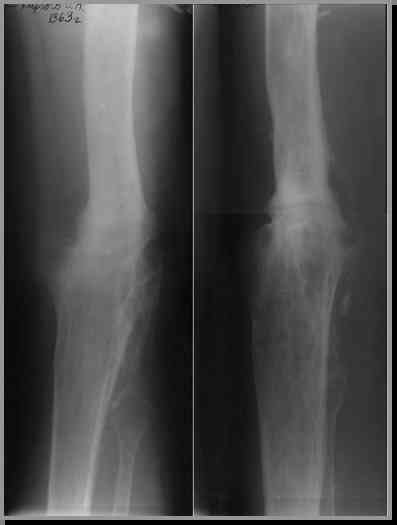

Прикрепляю пример замещения дефекта бедра 20 см, после резекции по поводу опухоли, эндопротеза Сиваша, вялотекущего остеомиелита со свищами в течении 3 лет. Получилось хорошо и всего за 6 месяцев в аппарате. Колена не было. У Вас случай сложнее. Это было в 1998г. Я работал в ЦИТО и у меня было 4 больных, я занимался им с утра до ночи. Сейчас 60 больных и операций в нашем отделении 25-30 в неделю.Если могу чем помочь - нет проблем.